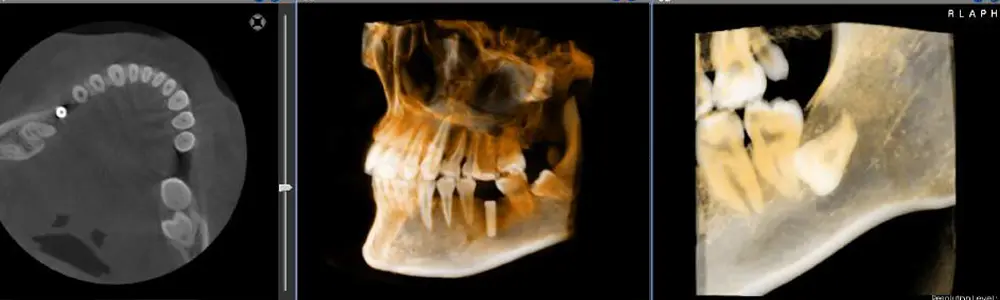

セファロ付き歯科用CT

歯科用CT・デジタルレントゲン

CTにより3D撮影が可能となり、より精密な術前診断等が可能となりました。また、当院のCTには、正確な矯正治療を行う上で、必須のツールの一つである「セファロ」機能も装備しているCTです。

矯正歯科用の特別なレントゲンであるセファロ(=顔面・頭部のX線撮影)は、世界共通の規格に基づき撮影を行い、顎の大きさや形態、上下の顎の位置関係、歯と顎の位置関係、歯の傾き、お口全体のバランスなど微細な情報を正確に把握でき、矯正治療の治療計画を立てる上で非常に重要です。